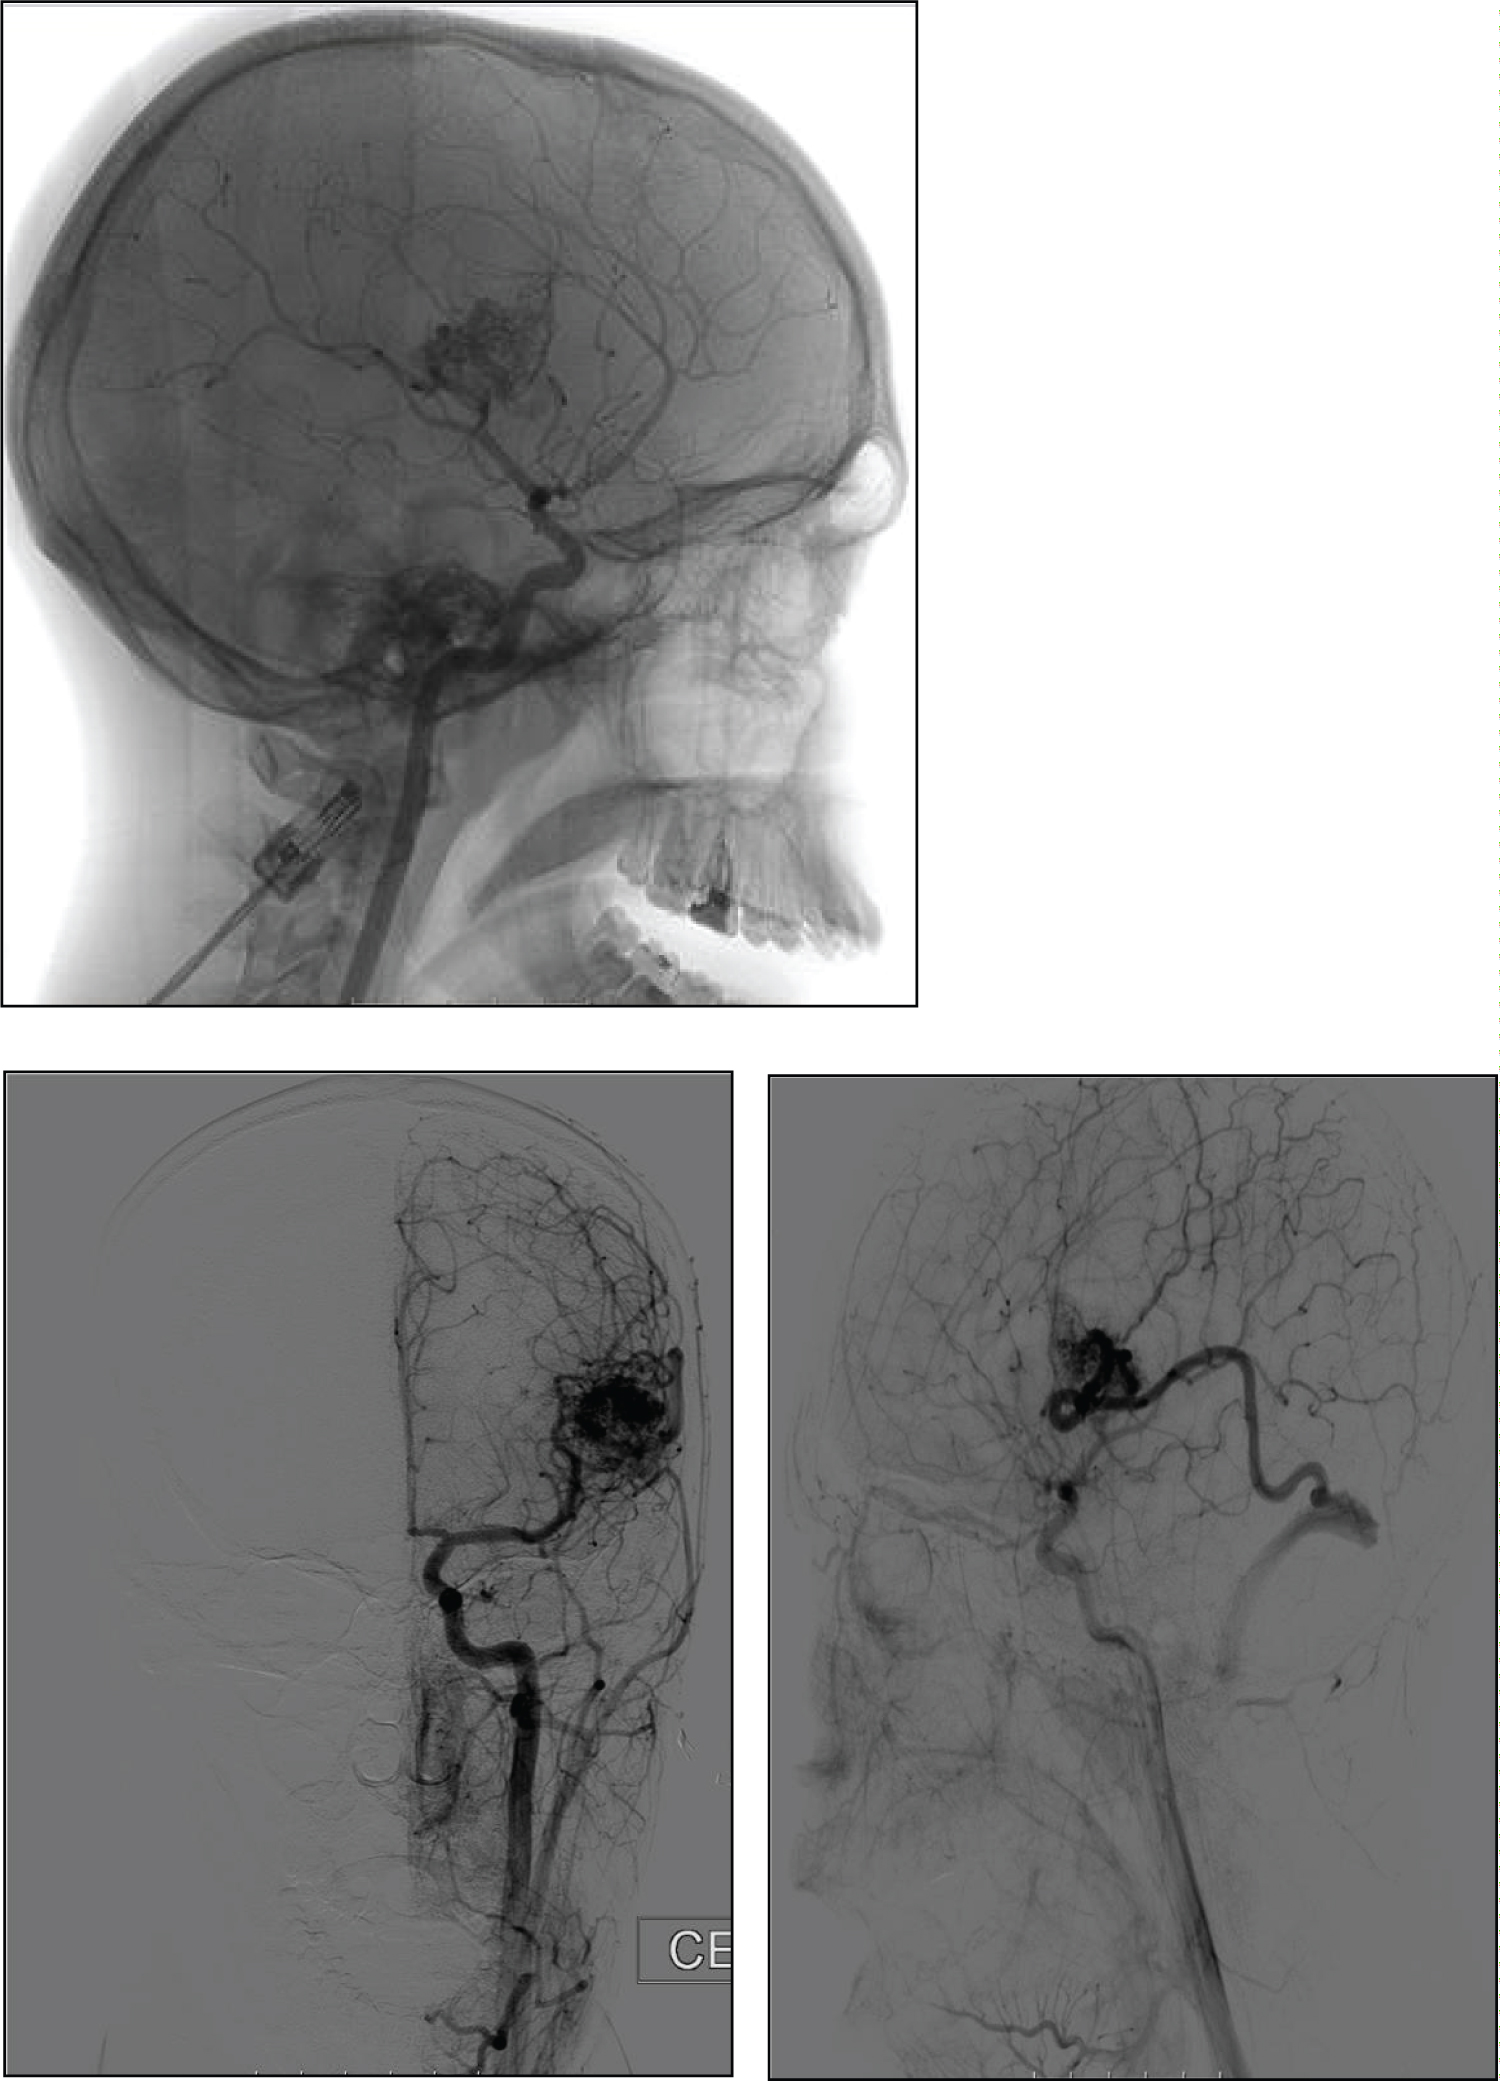

Cerebral angiography (Figure 2) confirmed the existence of a left frontal AVM nidus (2.1 × 2.3 cm) with predominant arterial supply from cortical branches of the middle left cerebral artery and superficial venous drainage to the left transverse sinus.

Figure 2: Cerebral angiography showing a left frontal AVM nidus with predominant arterial supply from cortical branches of the middle cerebral artery and superficial venous drainage to the left transverse sinus. View Figure 2